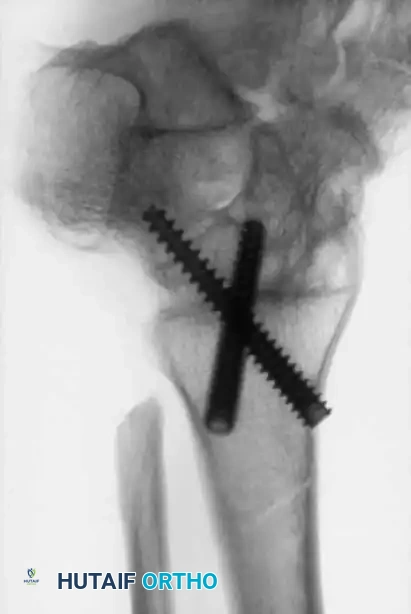

Image

Advanced hemophilic arthropathy of the ankle often requires aggressive intervention. When arthroscopic synovectomy fails to control symptoms in end-stage disease, definitive stabilization via ankle arthrodesis utilizing rigid internal fixation becomes necessary to eliminate pain and prevent further hemorrhagic episodes.